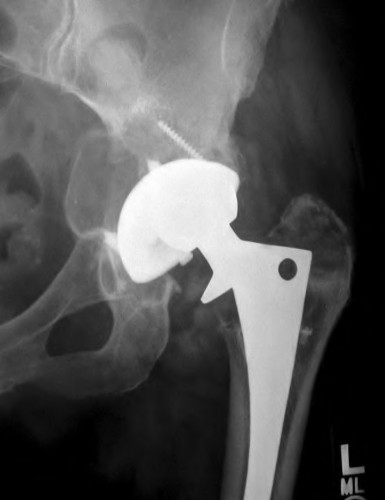

A 67-year-old man who underwent total hip arthroplasty (THA) 4 years ago fell on to his right hip. His pre-injury right hip film is seen in Figure A while films of his current injury are seen in Figures B and C. Prior to the fall he had no thigh or hip pain. His ESR and CRP are within normal limits. During intraoperative assessment, the acetabular and femoral stems are found to be well fixed. What is the next best course of action?

This patient has a periprosthetic hip fracture at the level of the stem with a stable prosthesis, indicated open reduction and internal fixation as the treatment of choice.

The Vancouver Classification can be helpful in clinical decision-making regarding fixation versus revision of periprosthetic hip fractures of the proximal femur. A stable implant, by nature, does not need to be revised in the setting of adequate bone stock for fixation, but the ultimate test of stability should be in the operating room. Many fixation strategies are appropriate, but many implants include locking plate fixation for concerns of stress-shielded bone around the implant as well as use of unicortical fixation at the level of the stem.

Pike et al review the current trends in treating B1 fractures including locking plates with strut allografts, minimally invasive plate osteosynthesis (MIPO) and locking plates spanning femoral THA and TKA stems in selected patients. The authors conclude that no studies currently provide evidence establishing one

technique over the other and recommend treatment on a case by case basis.

Illustration A shows a possible fixation construct for this patient's fracture. The Vancouver Classification is seen in Illustration B and Illustration C represents an algorithm for treatment options.